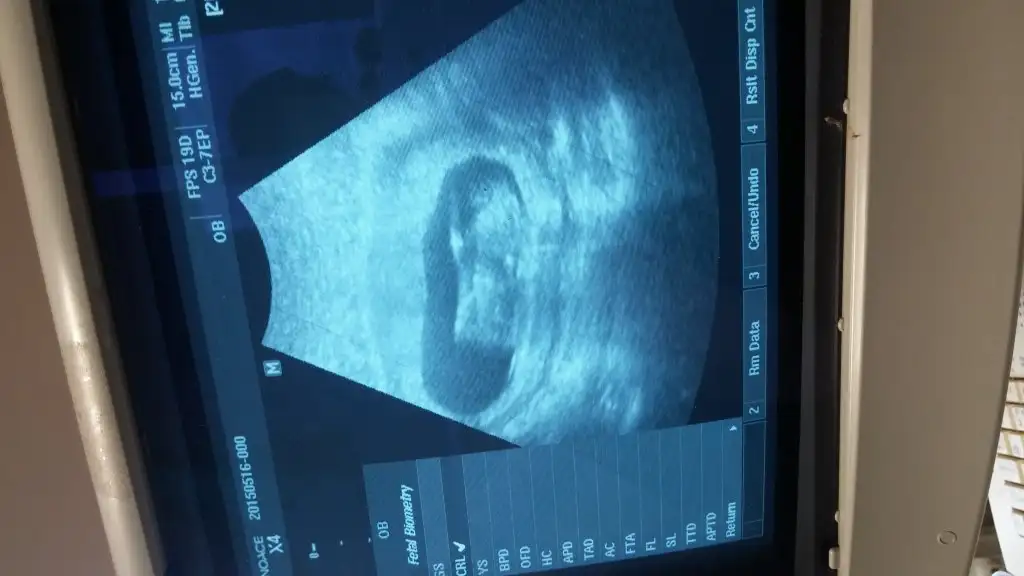

Sanki kiza benzettim benMerhaba, bugün randevumuz vardı ..goruntumuz aşağıda..10+1 haftalığız.. Belli oluyormu sizce, nedir cinsiyetimiz

erkek....Bi tahmnde bna yapablrmsnz :)

erkek...Kızlar gecen haftada paylaşmıştım karışık yorumlar geldi. Bu da bı haftaki. Yorum![]()